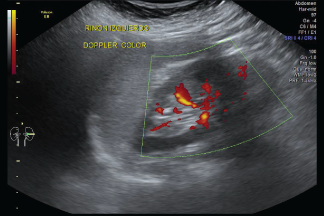

Ecografía Doppler Color

Las imágenes del ultrasonido son capturadas en tiempo real; eso es, no sólo muestran la estructura de una parte en particular del cuerpo, sino que también pueden mostrar el movimiento de los órganos internos así como el flujo de sangre a través de los vasos.

El doppler color permite precisar la dirección del flujo y distinción de una vena de una arteria, es necesario evitar presión sobre la mama para evitar compresión de los vasos, se necesita ajustar parámetros que permiten obtener óptima coloración en los vasos, filtro de pared lo más bajo posible, algoritmo adecuado para eliminar artefactos de movimiento, máxima ganancia.

Los ultrasonidos Doppler son importantes en el diagnóstico de lesiones mamarias porque un tumor maligno (canceroso) de masa puede tener irregularidades del flujo sanguíneo.